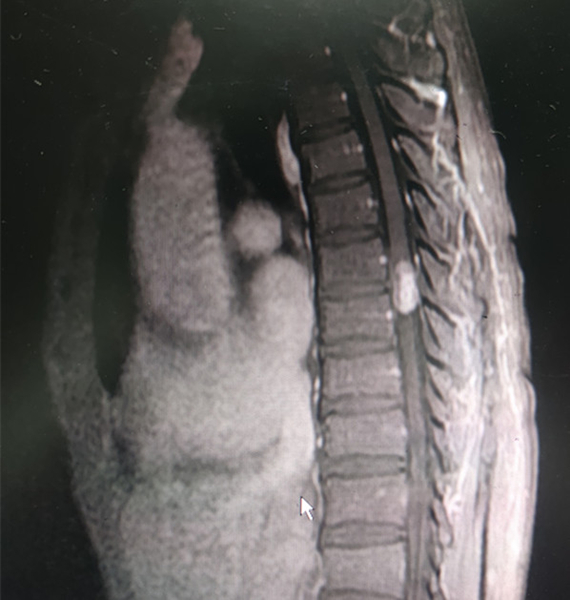

手術(shù)前MR影像

10月17日,60歲的男患者吳某因胸背部疼痛伴雙下肢麻痹入恩平市人民醫(yī)院外一區(qū)留醫(yī),入院后,醫(yī)院對(duì)其進(jìn)行胸椎增強(qiáng)MR檢查,發(fā)現(xiàn)脊髓胸7、胸8(第七至第八段胸椎)段有腫物,性質(zhì)未明。經(jīng)江門(mén)市中心醫(yī)院幫扶專(zhuān)家、脊柱外科副主任醫(yī)師趙振東診視病人并組織恩平市人員醫(yī)院骨科專(zhuān)家討論后,認(rèn)為椎管內(nèi)神經(jīng)鞘瘤可能性大,建議擇期行手術(shù)治療。

隨后,醫(yī)院完善對(duì)患者的相關(guān)檢查,并未發(fā)現(xiàn)其有手術(shù)禁忌癥。10月20日,趙振東帶同副主任醫(yī)師劉焯明及主治醫(yī)師馮華文順利進(jìn)行了胸椎全椎板切除減壓、脊髓內(nèi)腫瘤切除、胸椎釘棒內(nèi)固定術(shù),順利取出腫物,經(jīng)術(shù)后病理診斷,該腫物為椎管內(nèi)神經(jīng)鞘瘤。其后,經(jīng)病理化驗(yàn),確定其為椎管內(nèi)神經(jīng)鞘瘤。術(shù)后第二天,患者雙下肢麻痹癥狀明顯改善,對(duì)其胸椎段復(fù)查MR,顯示腫瘤影消失,脊髓形態(tài)正常。